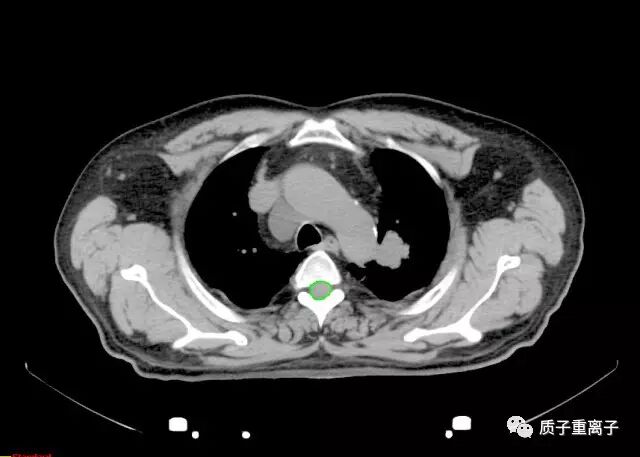

质子治疗前检查图像:左肺上叶见直径3.9cm肿块影;

质子治疗剂量分布:剂量分布良好,对周围正常组织能起到很好的保护,对肿瘤能给予致死剂量: